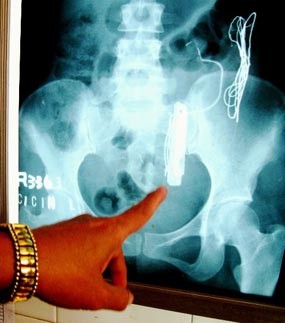

Perut Berisi Kawat dan Logam

Sepekan Dirawat di RS, Cicin Meninggal Dunia